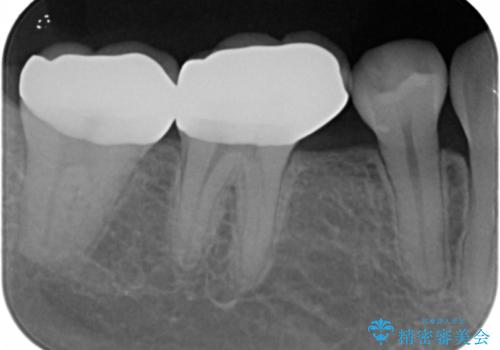

- 奥歯の隙間を治したいとご希望された患者様です。

学生時代に舌側矯正されていたものの、通院が大変になり治療を途中でやめてしまい、奥歯の間に隙間が残ってしまったそうです。

矯正せずに早く治したいという強いご希望とう蝕があることから、セラミッククラウンによる補綴治療で隙間を閉じることにしました。

クラウンの種類:オールセラミッククラウン スタンダード